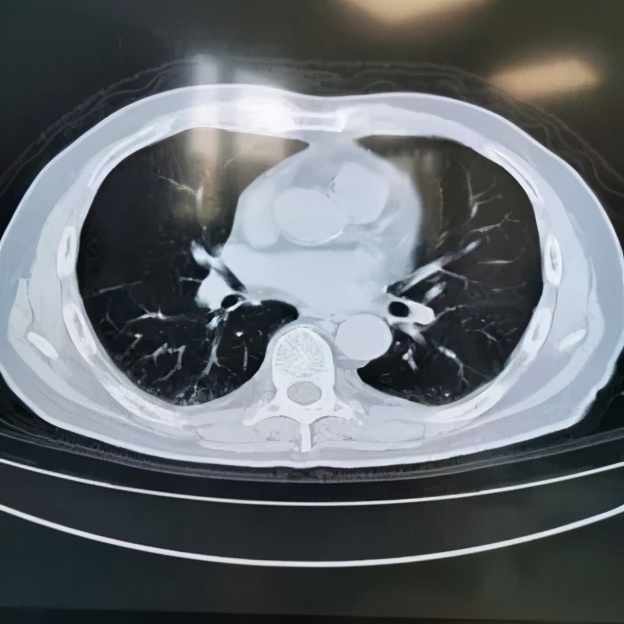

本院胸部CT(2019-08-30)示: 双肺弥漫性间质性改变,有网格状改变、毛玻璃影、局部有支气管牵拉形成支气管扩张的表现。

动脉血气(09-02):PaO2:68mmHg,PaCO2:35mmHg。动脉血气(09-11):PaO2:65mmHg,PaCO2:37mmHg。胸CT和肺功能都指向肺弥漫性间质性病变。

追溯患者2018年体检胸部CT(2018-1-22) :两肺下叶轻度间质增生,无显著双肺弥漫性间质改变。而且近一个月出现气促症状、低氧血症,说明间质性病变有活动性。